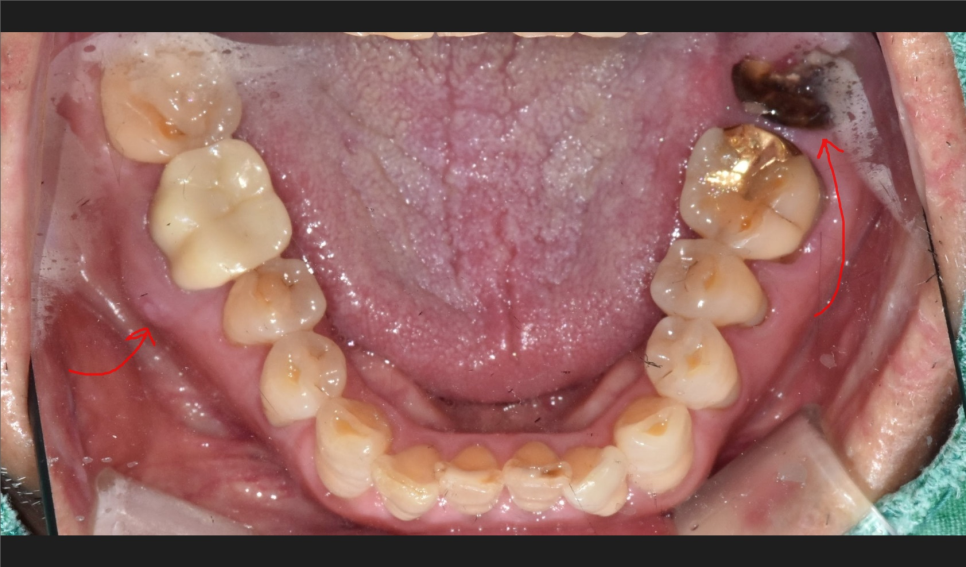

먼저 치과치료의 가장 기본에 해당하는 X-ray들을 보겠습니다.

어금니에 잇몸이 안좋아보이는 부분들이 몇군데 보이는군요.

우선 급한쪽부터 치료를 원하신다는 환자분의 요청에 따라

뿌리만 남은 치아를 먼저 하기로 결정합니다.

뼈이식과 봉합까지 모두 마무리한후 찍은 사진입니다.

2달이 지났습니다. 임플란트가 잘 붙은것을 확인하고

임플란트 상부 보철물 제작을 진행합니다.

반대편에 고름주머니 잡힌 치아도 발치 즉시 식립으로 수술을 원하셔서

당일 수술 진행해 드렸습니다.